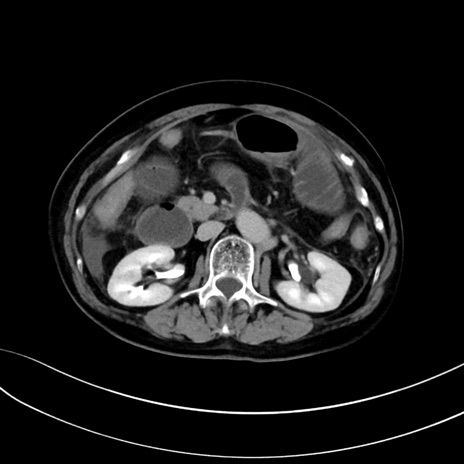

症例13 CT(横断像)1日半後